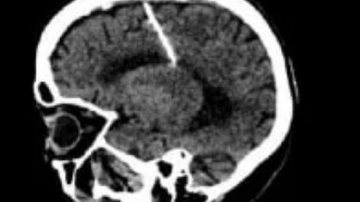

Um jovem foi morto com três tiros na cabeça quando voltava do trabalho no bairro Angelim, Teresina (PI), na tarde deste sábado. A vítima foi identificada como Mateus.

De acordo com o sargento Pereira, do 22° Batalhão da Polícia Militar, o jovem morava no bairro e estava voltando do trabalhando quando foi abordado por três homens em um carro branco que atiraram contra ele.